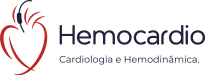

Angioplastia coronariana

Procedimento terapêutico realizado para desobstruir uma artéria coronária, na maioria das vezes com implante de um dispositivo de metal chamado "stent" que comprime a placa obstrutiva sob a parede do vaso, devolvendo ao vaso seu calibre normal. Pode ser feito de forma eletiva (programada) ou de emergência, como nos casos de infarto agudo do miocárdio.